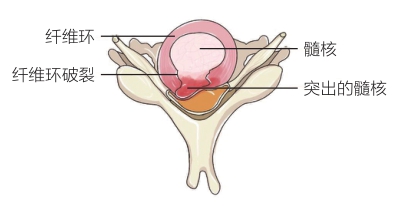

腰椎间盘突出症是指腰椎间盘的纤维环破裂和髓核组织突出,压迫和刺激相应水平的神经根,从而引起一系列症状和体征。

1.膨出型,纤维环部分破裂,表层完整。

2.突出型,纤维环完全破裂,髓核凸向椎管。

3.脱出型,突出的髓核穿破后纵韧带,呈菜花样。

4.脱垂游离型,大块髓核组织完全突入椎管内。